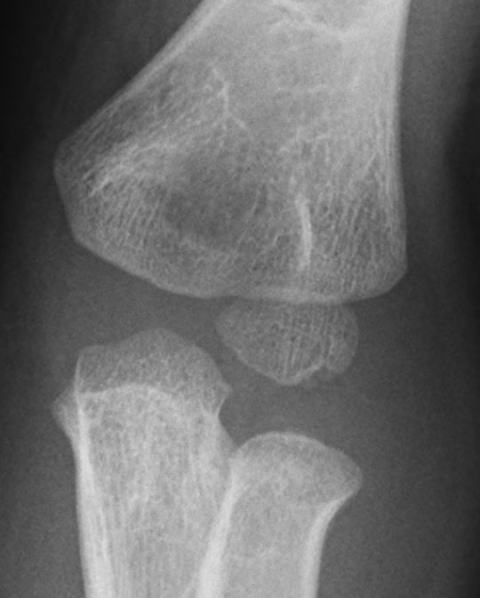

上腕骨小頭骨端核の無腐性骨壊死で、同部の離断性骨軟骨炎(OCD;osteochondritis dissecans)との鑑別が難しい。発症年齢が4-10歳と若く、レントゲン所見も上腕骨外側顆骨端核全体の不整像とまだらな透亮像を認める。

(離断性骨軟骨炎は10歳以上で、レントゲンでは上腕骨小頭前外側部に限局した病変を認めることが多い)

オーバーヘッドの運動を繰り返す子供の利き腕に起こることが多い。また外傷後に生じる例も報告されている。通常は、肘の痛みや可動域制限を訴えて来院する。レントゲン像は多彩であるとされる。経過中に、萎縮して分節化し、その後、再生していく経過をたどることが多いとされる。